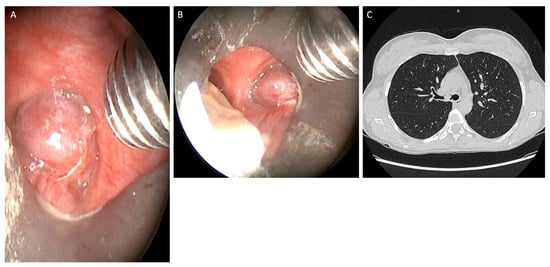

Hemostasis of the tumor implant base was obtained preventively using the argon plasma laser [11] or Thulep Laser (Revolix, Lisa Laser Producer OMG, Katelenburg, Germany) with high pulse-emission frequencies (up to 1000 Hz), in view of the high bleeding risk of these tumors, then tumor clearance was mostly performed by mechanical debridement and excision with the use of forceps and aspirator through the working channel of the 8.5 mm-sized rigid bronchoscope (Figure 2).

Figure 2. (A,B) Clearance of tumor was mostly performed by mechanical removal and through the working channel of the rigid bronchoscope of size 8.5 mm.